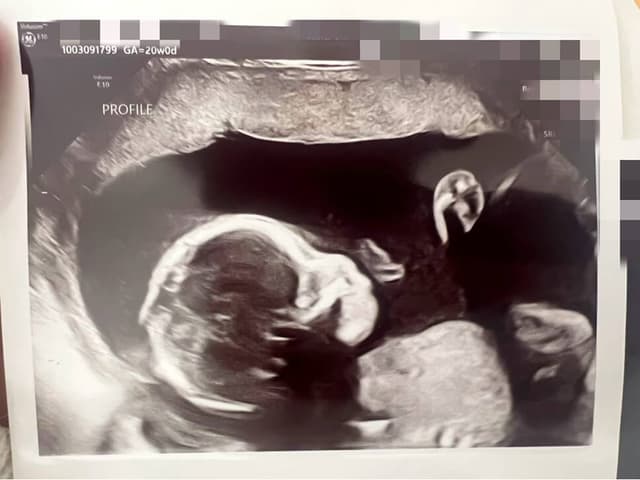

Our connection to surrogacy began with Cherry's own experience. After facing significant challenges during her first pregnancy, she welcomed her second child with the help of a Gestational Carrier. Throughout the entire process, Jane stood beside her — as a friend, a researcher, and a constant source of strength. Together, we navigated the doctors, the emotions, the uncertainties, and the incredible moments of gratitude.

So, combining first-hand experience, deep empathy, and the strength of a friendship built on trust, we created Twinkle — a place where families can grow, where GCs are honored, and where every path to parenthood is treated with respect and love. Over the past three years since our founding, we have provided consulting services to 500+ families and have successfully facilitated over 100 matches. (Our first client's surro baby we delivered was just born 3 days after Cherry's surro baby!